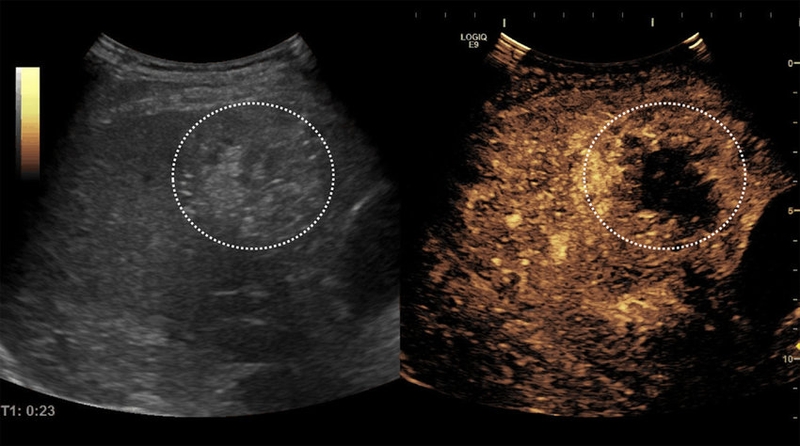

Siêu âm gan có phát hiện ung thư không? Câu trả lời là có, đặc biệt với sự hỗ trợ của công nghệ siêu âm tăng cường chất tương phản (Contrast-Enhanced Ultrasound – CEUS). Đây là một kỹ thuật tiên tiến được áp dụng phổ biến tại Hoa Kỳ, châu Âu và châu Á trong chẩn đoán ung thư gan, đặc biệt là ung thư biểu mô tế bào gan (Hepatocellular Carcinoma – HCC).

CEUS được sử dụng để xác nhận sự hiện diện của các tổn thương gan khu trú nghi ngờ là ung thư sau khi thực hiện các xét nghiệm chẩn đoán ban đầu như siêu âm ổ bụng hoặc xét nghiệm máu alpha-fetoprotein (AFP). Đối với những bệnh nhân bị xơ gan, chỉ cần thực hiện CEUS mà không cần kết hợp với chụp CT hay MRI, bác sĩ đã có thể nhận diện được các dấu hiệu điển hình của ung thư biểu mô tế bào gan.

Điểm nổi bật của CEUS nằm ở khả năng thu được hình ảnh động, tương tự như hình ảnh từ CT hoặc MRI nhưng đồng thời còn có thể hiển thị đặc tính tưới máu cơ quan. CEUS giúp phân biệt rõ ràng giữa động mạch và tĩnh mạch cửa, qua đó nhận diện các dấu hiệu đặc trưng của ung thư biểu mô tế bào gan mà các phương pháp khác đôi khi bỏ sót, đặc biệt trong những trường hợp có hình ảnh không điển hình.